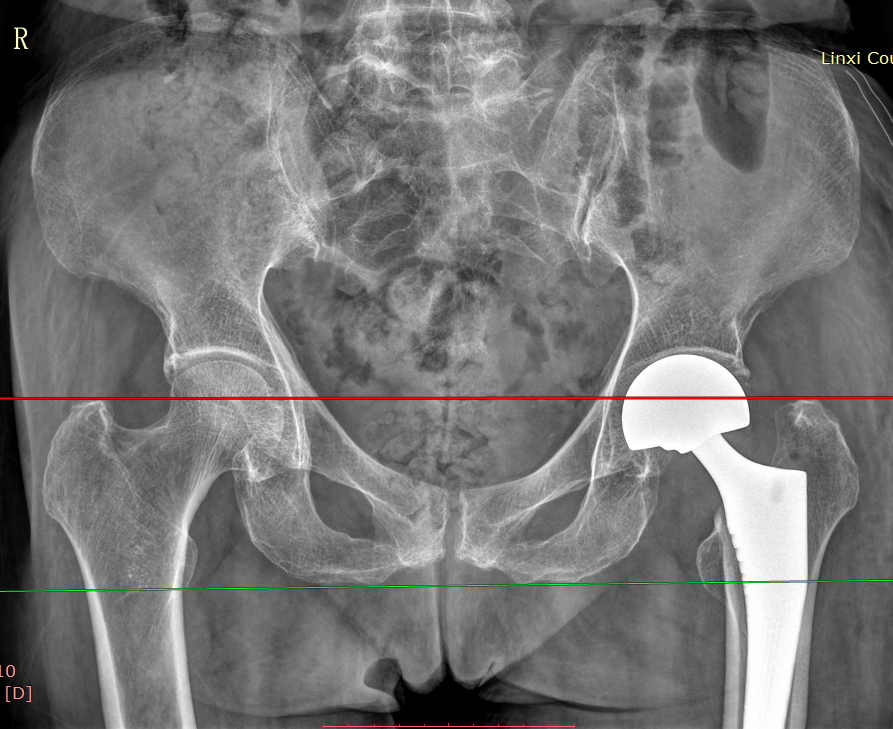

股骨颈骨折人工股骨头置换术(Artificial femoral head replacement for femoral neck fractures)